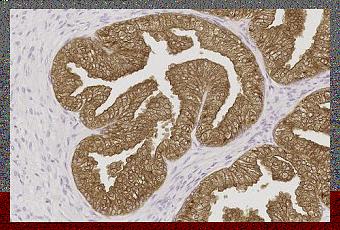

Prostate humaine : marquage immunohistochimique de l'antigène prostatique spécifique avec NCL-PSA-431. Notez le marquage cytoplasmique intense des cellules épithéliales glandulaires. Coupe en paraffine.

Source iconographique et légendaire:http://www.leicabiosystems.com/fr/ihc-ish/reactifs-novocastra/anticorps-primaires/details/product/prostate-specific-antigen/